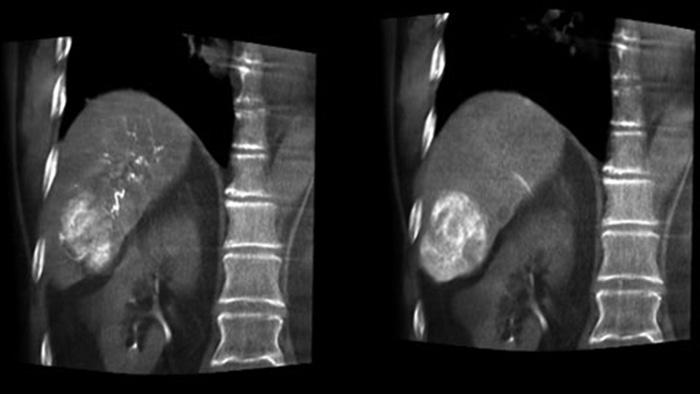

Imágenes 3D posteriores a la embolización con la THC

Una adquisición 3D posterior a la embolización le permite ver el depósito dirigido del material embólico, como Liopidol o perlas radiopacas, en el tumor.5.

Fusión de imágenes 3D antes y después de la embolización con Dual View

Dual View permite ver de forma simultánea la imagen 3D de la fase arterial antes de la embolización y la imagen después de la embolización para evaluar el fin del tratamiento.